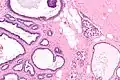

Collagenous spherulosis is characterized by a tubular/cribriform architecture with intratubular eosinophilic material that classically is arranged like the spokes of a wheel ("radial spikes"). There is usually no mitotic activity, and two cells populations (epithelial & myoepithelial) are present, like in benign breast glands.

The lesions are typically small (less than 50 spherules per lesion, less than 100 micrometers in size) and may be multifocal.